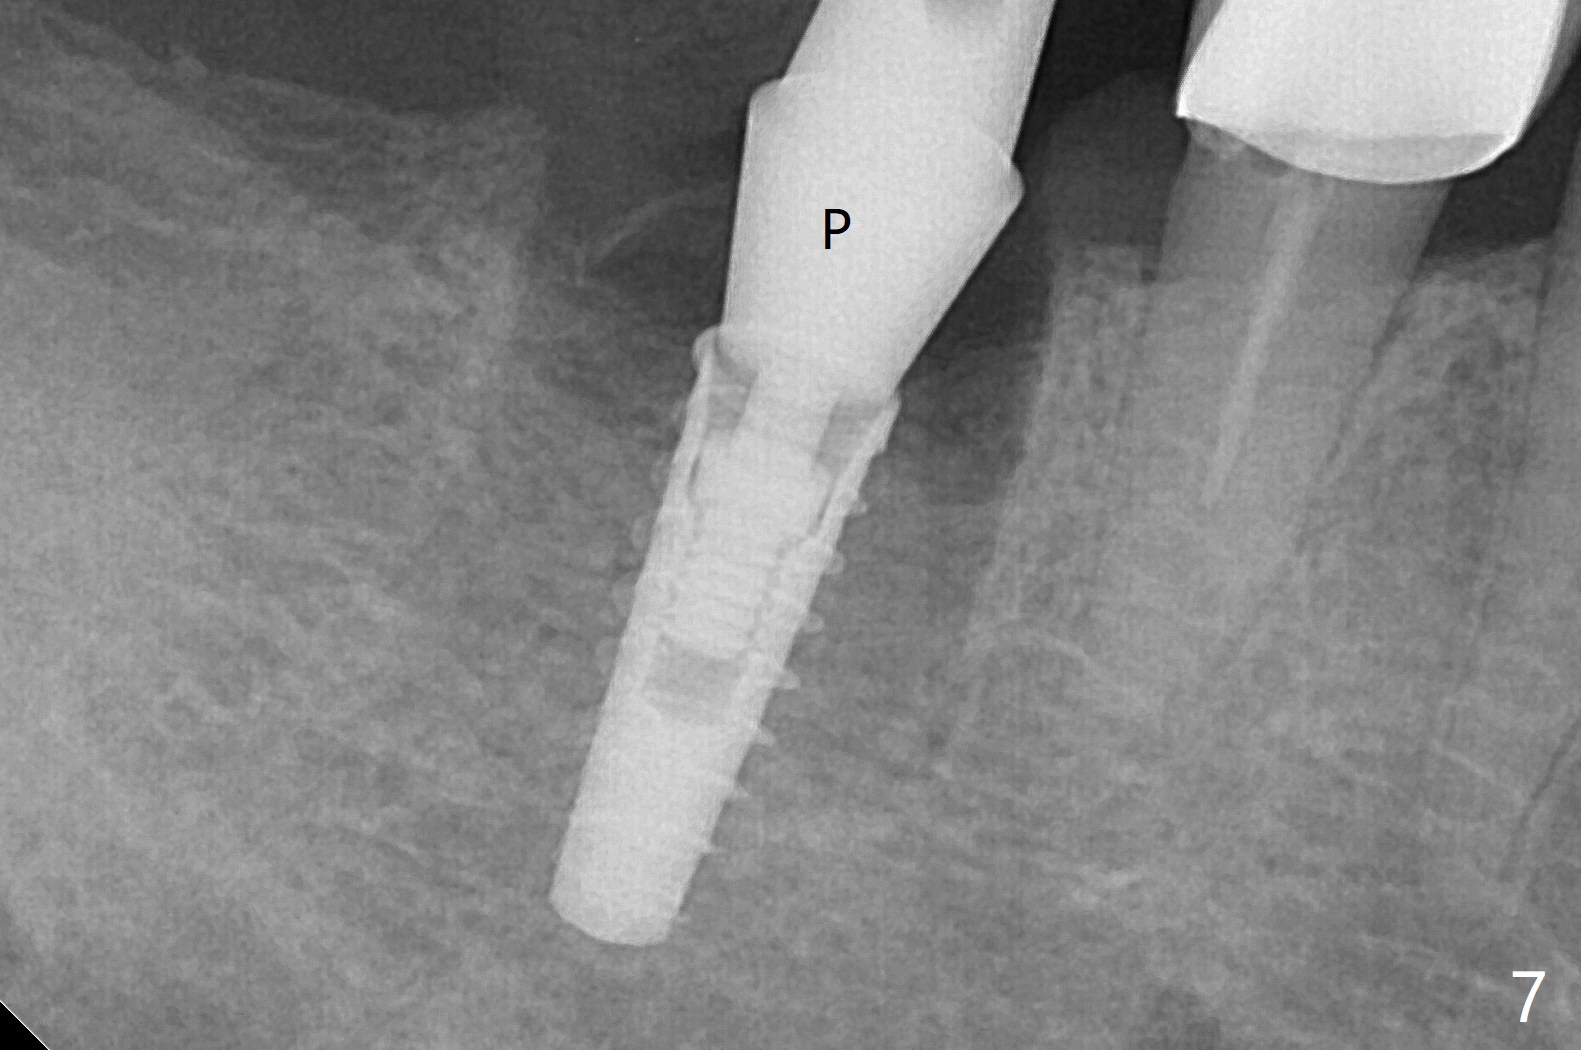

A 59-year-old woman with severe pain and mobility at #30 returns to clinic for extraction and implant on emergency basis (Fig.1 ^: crazing line). To prevent osteotomy deviation off the septum, the crown is sectioned (Fig.2) and the coronal end of the septum is exposed. In fact the initial osteotomy is blind (Fig.3). After increasing the access (Fig.4), trying to change trajectory and increasing the depth and diameter of the osteotomy, the trajectory deviates to the distal socket (Fig.5). Following root extraction, debridement of the sockets and minor trajectory change, a 4x11 mm dummy implant is placed (Fig.6). With a drastic change in osteotomy, the dummy implant position is somewhat acceptable with a 5.2x4 mm planning abutment (Fig.7 P). After placement of bone graft around the 4.5x11 mm final implant to enhance stability, a 5.5x4(3) mm definitive abutment is placed in a restorable position (Fig.8). The implant turns while the abutment screw is hand tightened. Since there is an apical space (Fig.8 <), the implant is then placed ~ 1mm deeper with ~ 30 Ncm (Fig.9). A longer cuffed abutment is inserted and more bone graft is placed (*). In summary, roots in the sockets do not seem to help free hand osteotomy in the lower 1st molar. It is also difficult to control pain during acute infection. Block anesthesia has to be administered, increasing the chance of nerve injury. Either guided surgery or delayed implant should be conducted. There is no postop paresthesia, although the buccal gingiva is slightly erythematou, edematous and tender 1 week posotp. Oral Amoxicillin is prescribed for one more week. The keratinized gingiva (Fig.10 ^) and the papilla (*) are maintained in place around the immediate provisional (P) 2 months 20 days postop. The soft tissue remains normal 4 months postop (Fig.11) and immediate pre cementation (Fig.12).